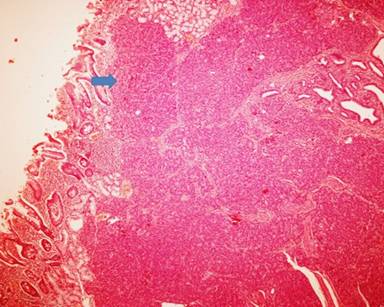

Histopathological examination of the surgical specimen from periampullary nodule showed ectopic pancreatic tissue composed of ducts, acini, and well-formed islets in the mucosa and submucosa of the duodenum (Figure 2). Focal area of mucosal ulceration was seen (Figure 3). Even on extensive sampling of the specimen there was no gross or microscopic evidence of malignancy seen.

Figure 2. Histopathology section showed ectopic pancreatic tissue composed of ducts, acini, and well-formed islets in the mucosa and submucosa of the duodenum (arrow). |